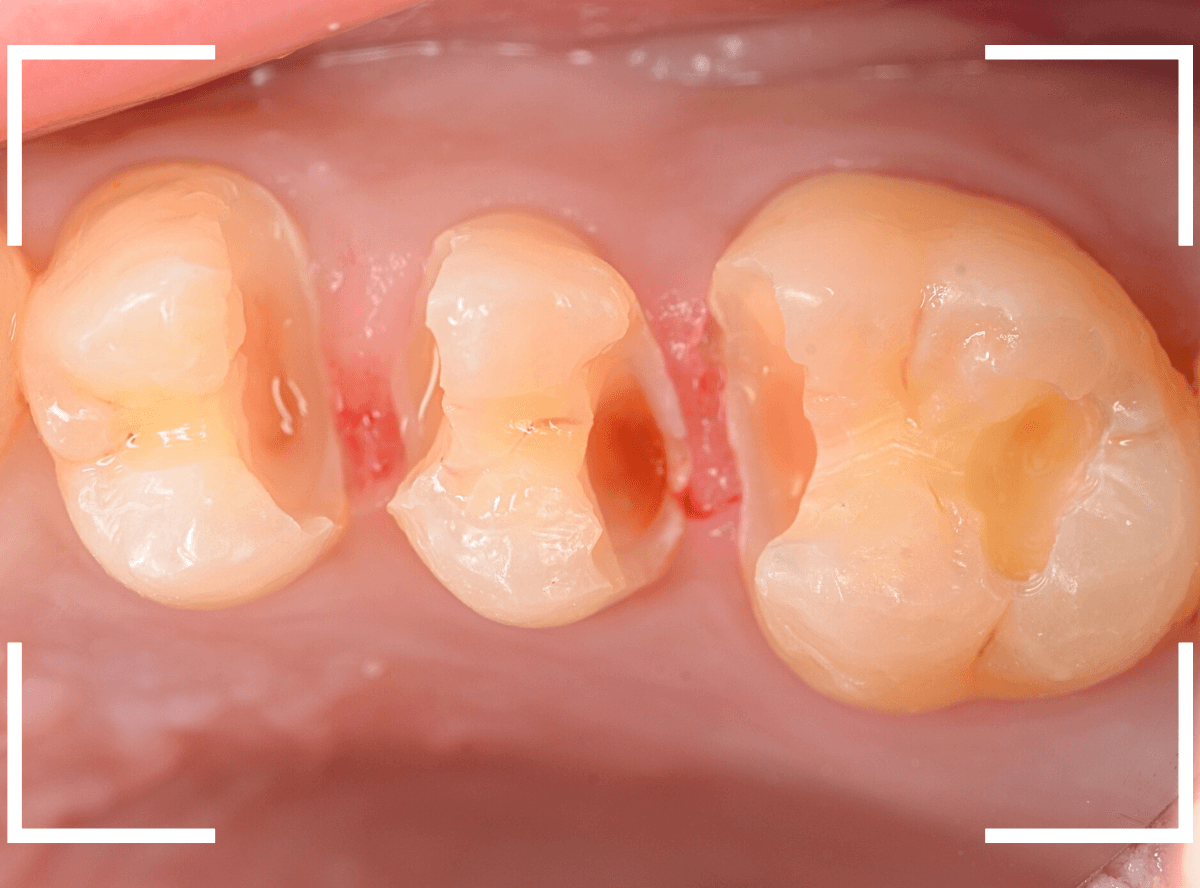

Case.6 レジンの下であちこちから虫歯

今回も、白いつめ物(レジン)の中が大きな虫歯になっていたお話です。

何度か虫歯治療をしたのか、つめもの(レジン)がつぎはぎになっています。

レントゲン写真で確認します。

虫歯が確認できますが、つぎはぎの治療のためか、状況がちょっとわかりづらい写りになっています。

レジンを少しずつ除去して虫歯を探っていきます。

あちこちから虫歯になっていますね。。。

う蝕検知液で途中確認します。

まだかなり虫歯が残ってる感じですね、また隣の歯のレジン中も怪しいので、外して調べる必要があります。

最終的に、かなり広範囲にわたる虫歯でした。

治療後にしみるなどの症状がないか、どのような方法で最終修復をするのがベストか、少し悩みの残る治療でした。